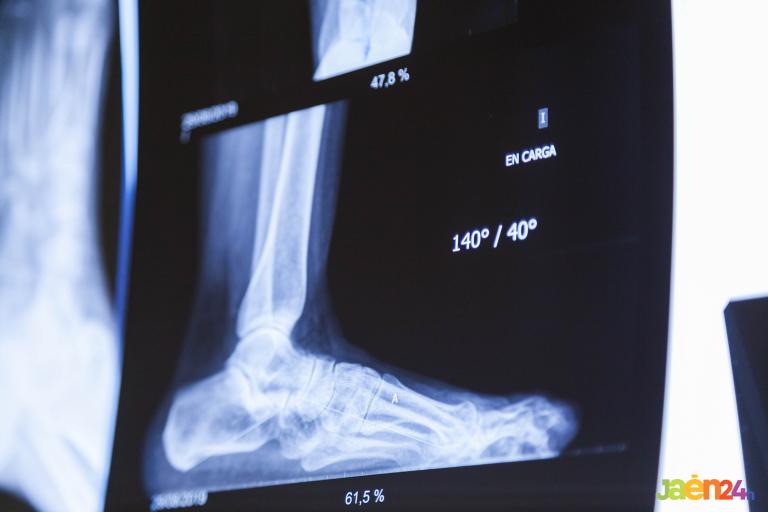

• Cirugía del pie, infiltraciones,

• Análisis biomecánico,